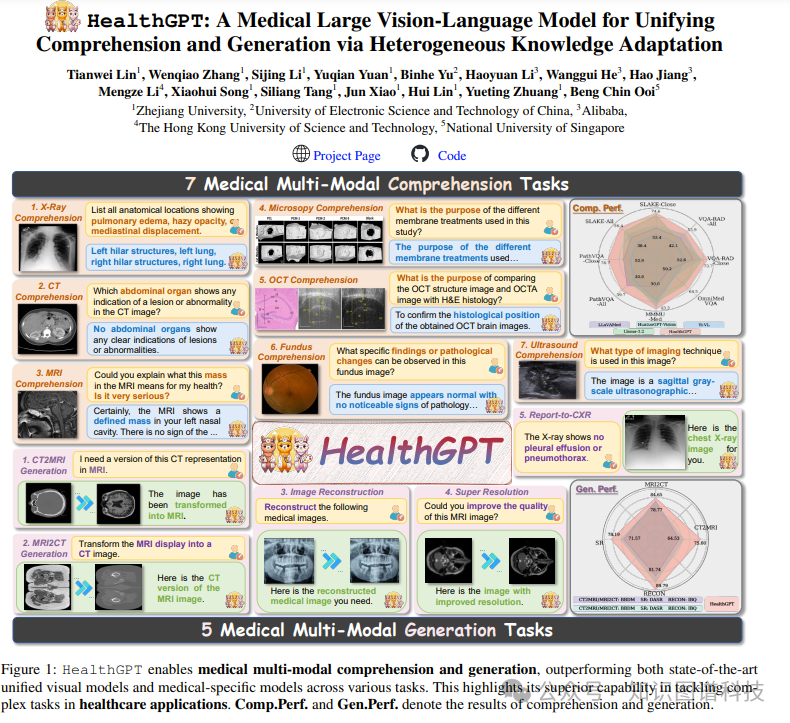

我们提出了一个强大的医疗大型视觉语言模型(Med-LVLM)HealthGPT,它在一个统一的自回归范式中整合了医疗视觉理解与生成能力。我们的引导原则是逐步适应异构的理解与生成知识到预训练的大型语言模型(LLMs)。这是通过一种新颖的异构低秩适配(H-LoRA)技术实现的,辅以定制的分层视觉感知方法和三阶段学习策略。为了有效学习HealthGPT,我们设计了一个全面的医疗领域特定理解与生成数据集,称为VL-Health。实验结果显示HealthGPT在医疗视觉统一任务中具有卓越的性能和可扩展性。我们的项目可以在

研究问题:这篇文章要解决的问题是如何在医疗领域统一视觉语言理解(NLU)和生成(NLG),以应对医疗应用中的复杂任务。

研究难点:该问题的研究难点包括:医疗数据的高规模和质量限制,以及理解和生成任务之间的冲突。具体来说,医疗数据的规模和多样性不足,且理解和生成任务需要不同的视觉细节处理方式,难以在同一模型中同时优化。

相关工作:该问题的研究相关工作包括:利用预训练的大型语言模型(LLMs)和视觉指令数据构建交互式诊断工具和治疗计划系统;开发能够跨多种视觉模态理解和生成内容的一体化LVLMs。然而,现有的研究和模型主要集中在视觉理解任务,缺乏医疗视觉生成能力,且未充分探索医疗领域的统一框架。

这篇论文提出了HealthGPT,一种用于解决医疗多模态理解生成问题的医学大型视觉语言模型(Med-LVLM)。具体来说,

HealthGPT架构:HealthGPT通过离散令牌表示同时覆盖文本和视觉输出,将视觉理解和生成任务统一为自回归任务。其架构结合了分层视觉感知(HVP)和异构低秩适应(H-LoRA)技术。

数据集:研究团队构建了VL-Health数据集,包括七个理解任务和五个生成任务。数据集涵盖了多种医疗图像模态和疾病类型,以确保模型的泛化能力。

理解任务:在多个医学视觉理解任务中,HealthGPT表现优于现有的医学特定模型和通用模型。例如,在医疗多模态统一任务中,HealthGPT-M3的得分达到了61.3,显著优于现有统一模型。

生成任务:在三个关键的医疗图像生成任务中,HealthGPT也表现出色:

模态转换:在CT到MRI的脑部和骨盆区域的转换任务中,HealthGPT-M3的SSIM得分为79.38,显著优于传统方法。

超分辨率:在IXI数据集上的4倍超分辨率实验中,HealthGPT-M3在SSIM、PSNR和MSE指标上均表现优异。

这篇论文提出了HealthGPT,一种用于医疗多模态理解生成的医学大型视觉语言模型。通过异构低秩适应技术和分层视觉感知,HealthGPT在多个医疗任务中表现出色,显著提高了医疗应用的多功能性和准确性。研究结果表明,HealthGPT在医疗视觉理解和生成任务中具有显著的性能提升和应用潜力。

统一的医疗多模态模型

:HealthGPT是第一个在复杂医疗场景中实现多模态理解和生成的统一框架。